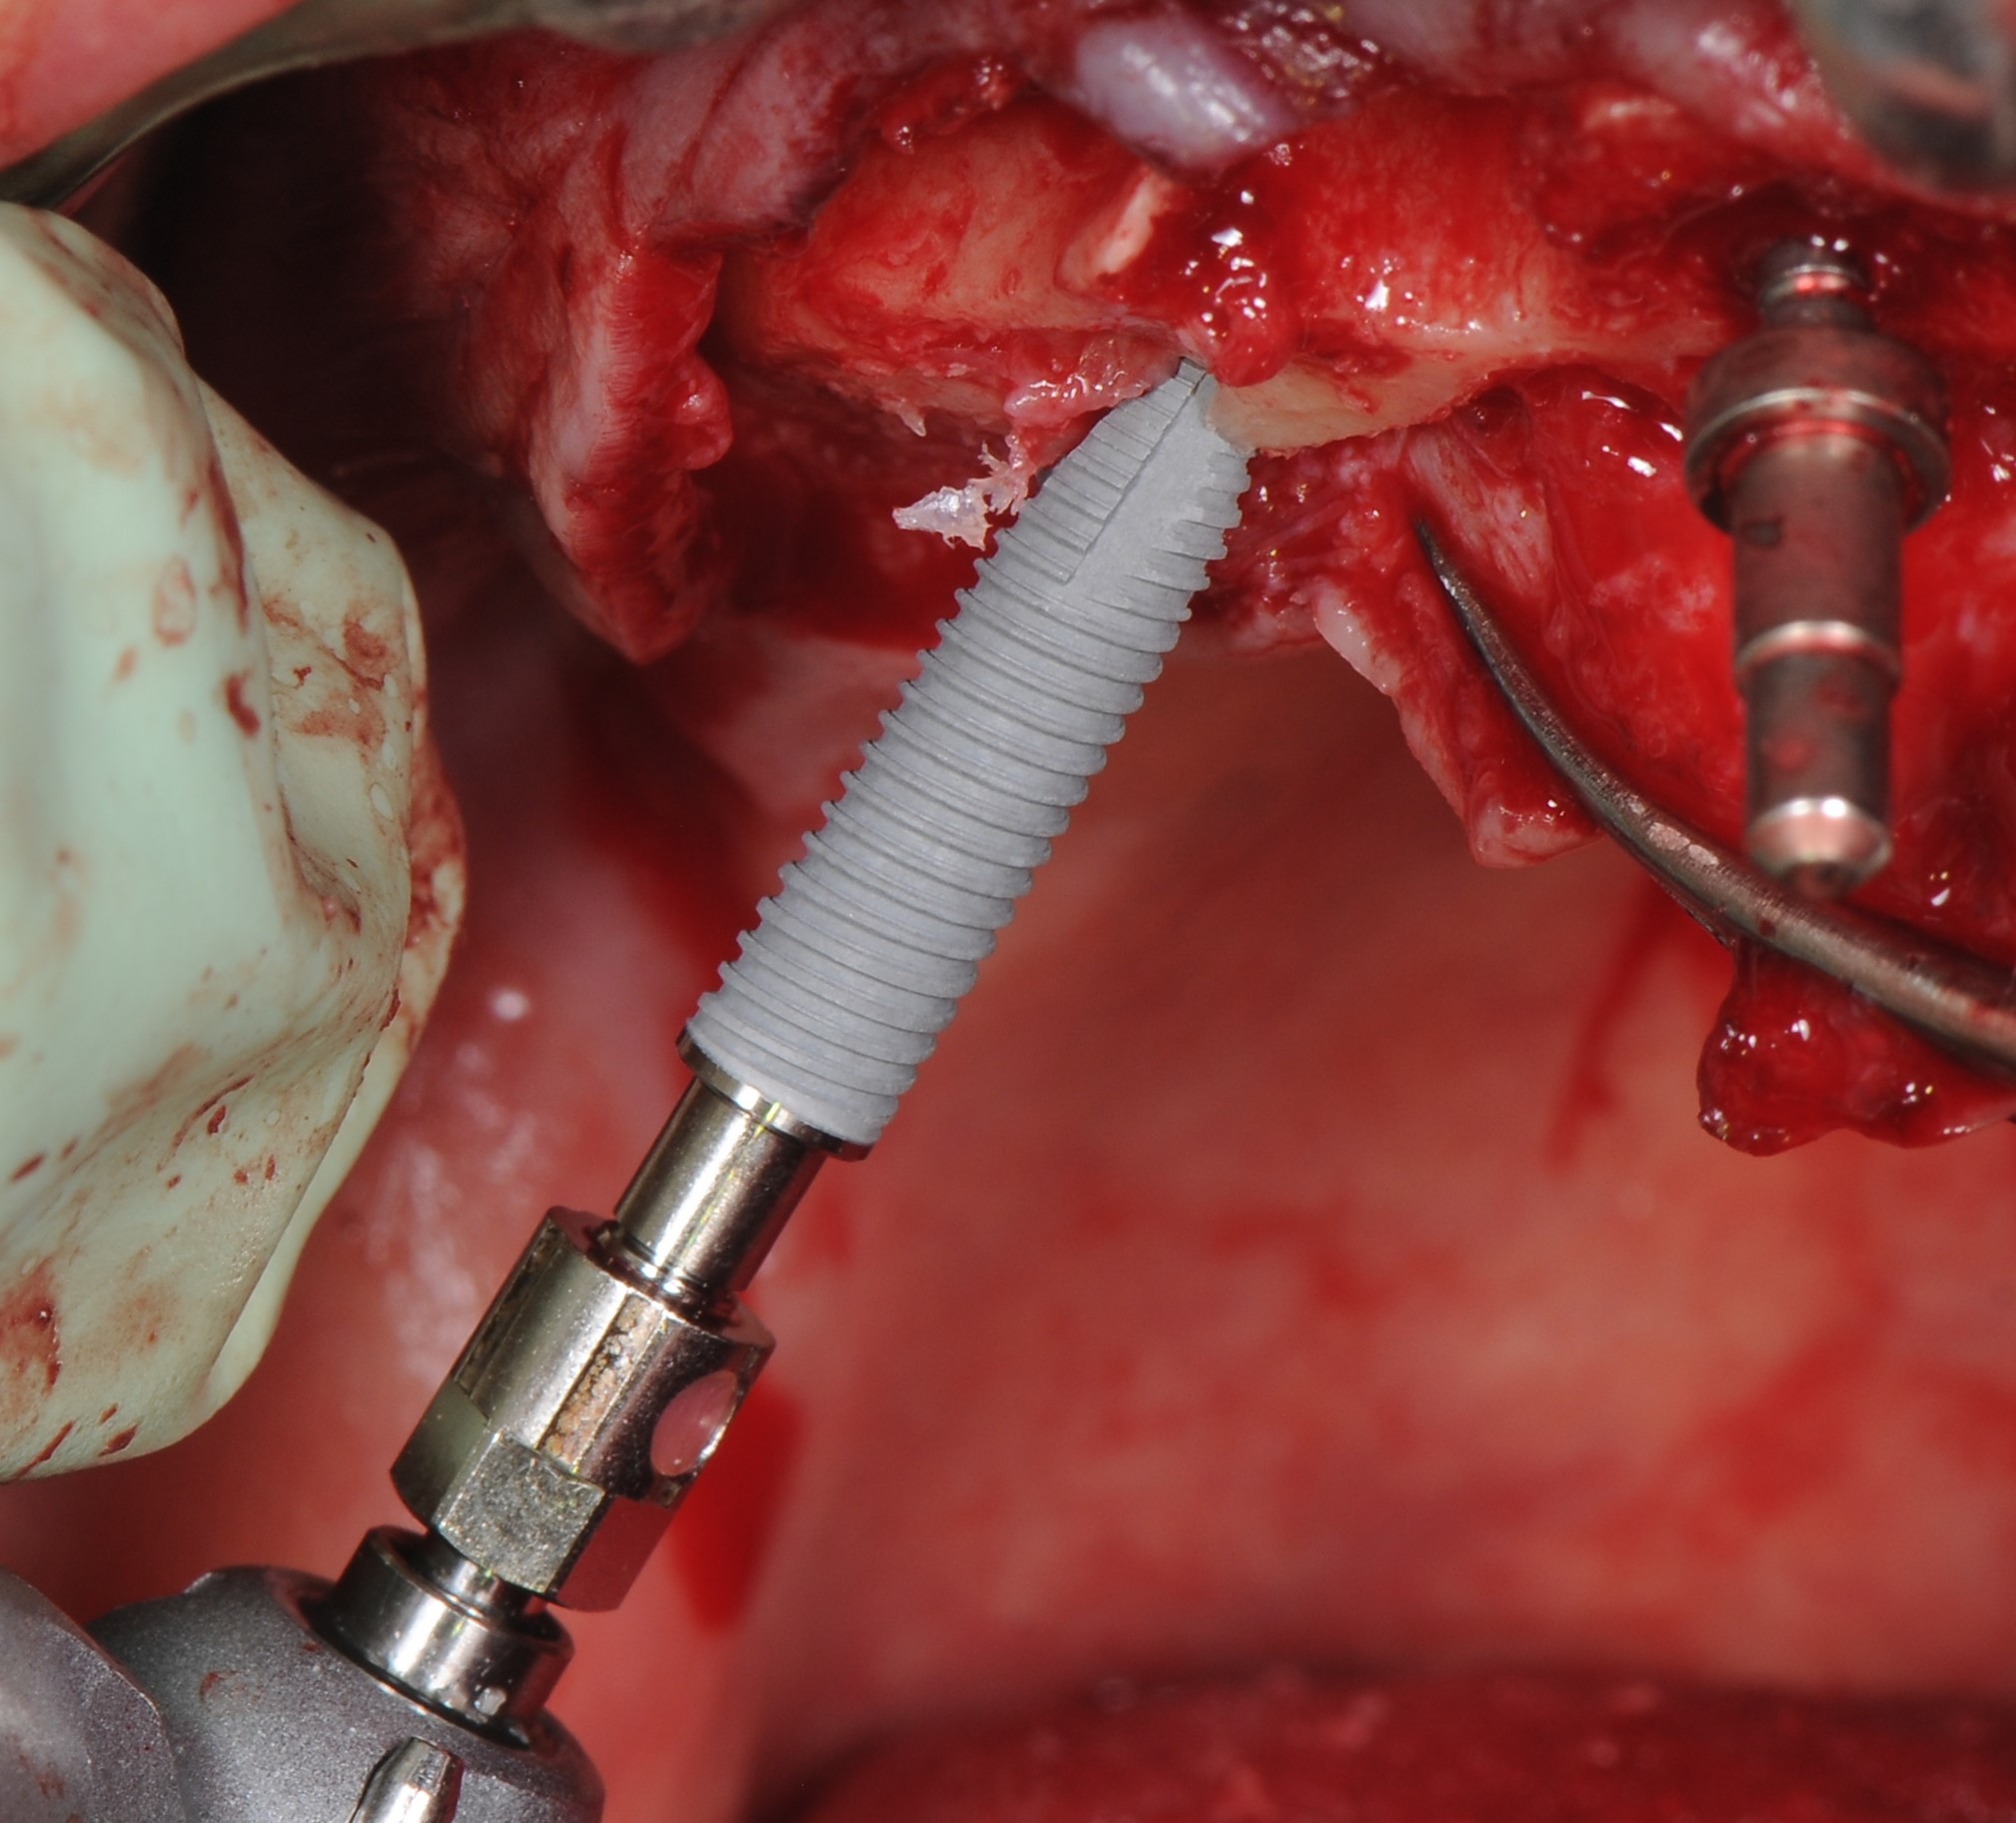

По протоколу неполного препарирования было выполнено формирование ложа для дентальных имплантатов «Nobel Parallel Conical Connection» с последующей их установкой по методике «All –on – 4». Дистальные имплантанты установлены под углом 30°, имплантаты во фронтальной зоне – вертикально(рис. 14-19). Торк (крутящий момент) всех установленных имплантатов составил более 35 N/см2 что, позволило нам одномоментно нагрузить все установленные имплантаты с установкой временного условно-съёмного протеза из акриловой пластмассы с титановым каркасом.

На имплантаты были установлены абатменты для винтовой фиксации «Multi – unit»: в боковых участках угловые 30О абатменты , во фронтальных участках – прямые абатменты (рис. 20,21)